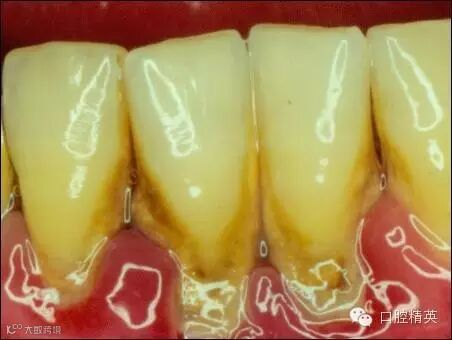

挂满了结石的牙龈组织红肿